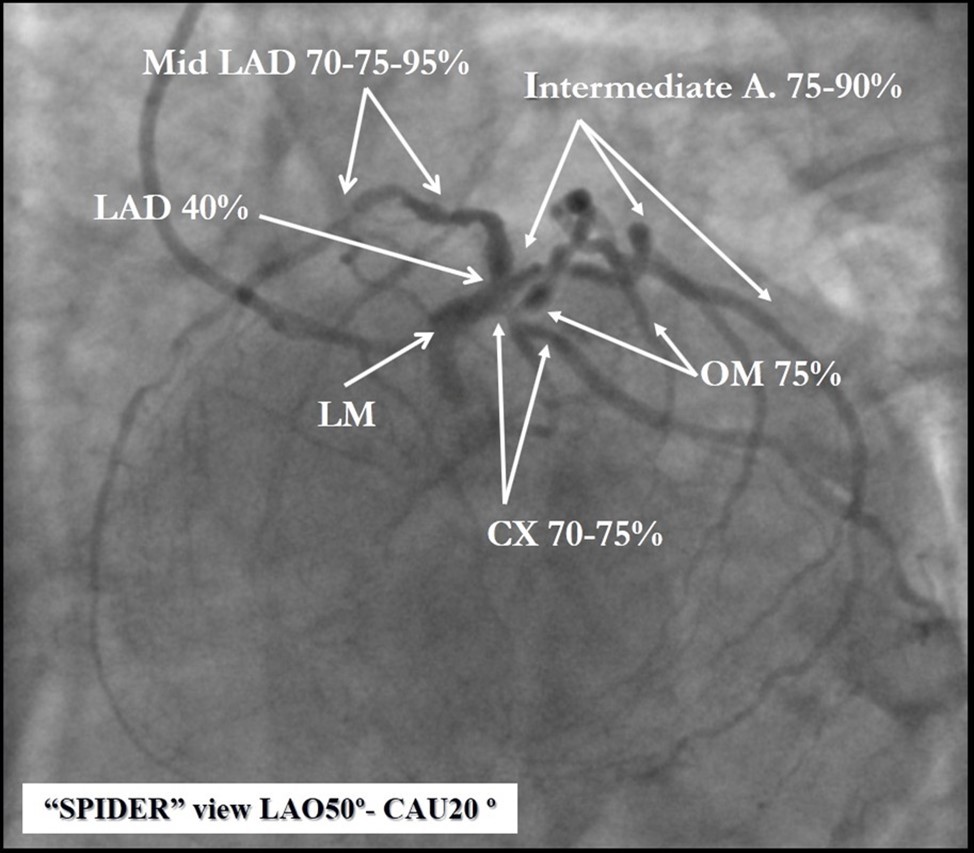

Angiography revealed rare anatomical variation LMCA quadrifurcation (Figure 1, Figure 2), 50% stenosis of the distal part of the LMCA, 40% stenosis of the ostial segment of left anterior descending (LAD) artery and diffuse prolonged 70-75-95% stenosis in mid-segment (Figure 3), 75% stenosis of the ostial segment of the circumflex (CX) artery, 75% stenosis of the ostial segment of the first marginal branch (OM1), 75-90% stenosis of the proximal segment of the intermediate artery (IMA), prolonged diffuse severe 90-95% stenosis of mid-segment of the right coronary artery (RCA) (Figure 4).

Figure 1.Quadrifurcation of the left main coronary artery